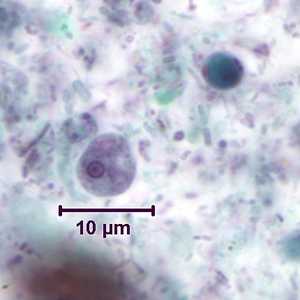

Iodamoeba buetschlii cysts in concentrated wet mounts.

Figure A: Cyst of I. buetschlii in an unstained concentrated wet mount. In these cysts, the glycogen vacuole can be seen as a large, oval refractile body.

Figure B: Cyst of I. buetschlii in an unstained concentrated wet mount. In these cysts, the glycogen vacuole can be seen as a large, oval refractile body.

Figure C: Cyst of I. buetschlii from the same specimen as seen in Figures A and B, but stained with iodine. In this cyst, the glycogen vacuole is more-easily observed as a dark-staining mass in the cyst.

Figure D: Cyst of I. buetschlii from the same specimen as seen in Figures A and B, but stained with iodine. In this cyst, the glycogen vacuole is more-easily observed as a dark-staining mass in the cyst.

I. buetschlii cysts stained with trichrome.

Figure A: Cyst of I. buetschlii stained with trichrome. In this specimen, both the nucleus and large glycogen vacuole are visible.

Figure B: Cyst of I. buetschlii stained with trichrome. In this specimen, both the nucleus and large glycogen vacuole are visible.

Figure C: Cyst of I. buetschlii stained with trichrome. In this specimen, both the nucleus and large glycogen vacuole are visible (arrow).

Figure D: Cyst of I. buetschlii stained with trichrome. In this specimen, both the nucleus and large glycogen vacuole are visible.